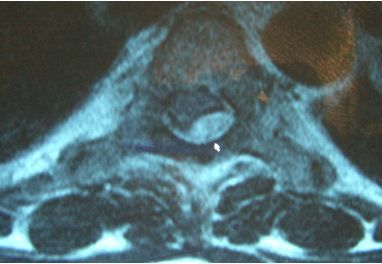

An obese woman presented with worsening back pain that extended from below her neck to her waist in the midline. She had been constipated and had difficulty urinating. Both legs started to feel “wobbly” and numb. The presence of fever and back pain indicated she had meningismus. This MRI scan shows a spinal epidural abscess (SEA; white arrow). The diagnosis of SEA often is late because its presentation is indolent and most patients who present with similar complaints have other, less serious conditions.